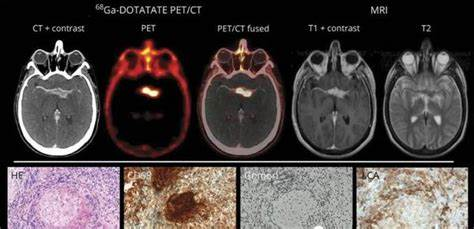

1. 皮层精准制导:7T核磁共振定位异常活跃的Heschl回区域

· 治疗后静息态fMRI显示,默认网络与听觉皮层连接强度恢复82%